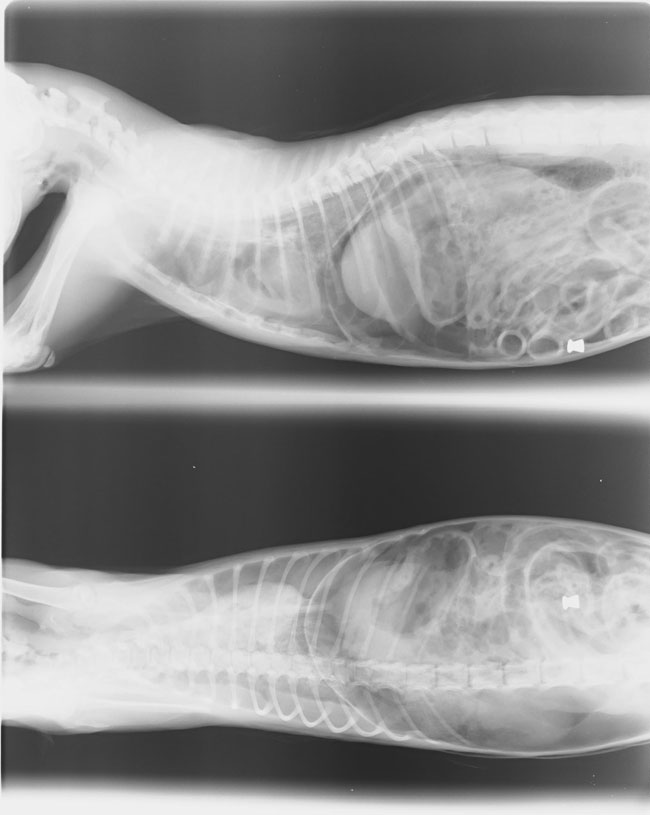

Muere un gato en Talavera a causa de un disparo de balín.

El pasado día 11 de julio un vecino del barrio talaverano de Patrocinio contactó con la Protectora de Animales "Amibichos" para informar de lo sucedido a uno de los gatos a los cuales cobija y alimenta en su chalet de la calle Puerto de San Vicente. El animal, un cachorro de gato de unos 5 meses de edad, había sido encontrado malherido en su patio falleciendo al poco tiempo. En la clínica veterinaria certificaron que había sido a causa del disparo de un balín, el cual atravesó la cavidad torácica provocando ruptura y hemorragia pulmonar y finalmente la muerte del animal.